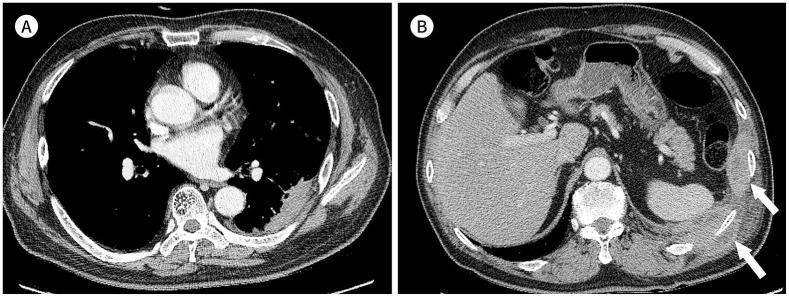

Immunoglobulin G4-related disease (IgG4-RD) is a chronic inflammatory condition involving multiple organs, including the salivary or lacrimal glands, orbit, pancreas, bile duct, liver, kidney, retroperitoneum, aorta, lung, and lymph nodes. It is histologically characterized by tissue infiltration with lymphocytes and IgG4-secreting plasma cells, storiform fibrosis, and obliterative phlebitis. In the thoracic involvement of IgG4-RD, mediastinal lymphadenopathy and perilymphangitic interstitial thickening of the lung are the most common findings. Peribronchovascular and septal thickening and paravertebral band-like soft tissue are characteristic findings of IgG4-RD. Other findings include pulmonary nodules or masses, ground-glass opacity, alveolar interstitial thickening, pleural effusion or thickening, mass in the chest wall or mediastinum, and arteritis involving the aorta and coronary artery. Radiologic differential diagnosis of various malignancies, infections, and inflammatory conditions is needed. In this review, we describe the imaging findings of IgG4-RD and the radiologic differential diagnoses in the thorax.

免疫球蛋白G4相关性疾病(IgG4-RD)是一种累及多个器官的慢性炎症性疾病,这些器官包括唾液腺或泪腺、眼眶、胰腺、胆管、肝脏、肾脏、腹膜后、主动脉、肺和淋巴结。其组织学特征为淋巴细胞和分泌IgG4的浆细胞浸润组织、席纹状纤维化和闭塞性静脉炎。在IgG4-RD累及胸部时,纵隔淋巴结肿大和肺淋巴管周围间质增厚是最常见的表现。支气管血管周围和小叶间隔增厚以及椎旁带状软组织是IgG4-RD的特征性表现。其他表现包括肺结节或肿块、磨玻璃影、肺泡间质增厚、胸腔积液或增厚、胸壁或纵隔肿块以及累及主动脉和冠状动脉的动脉炎。需要对各种恶性肿瘤、感染和炎症性疾病进行影像学鉴别诊断。在本综述中,我们描述了IgG4-RD的影像学表现以及胸部的影像学鉴别诊断。